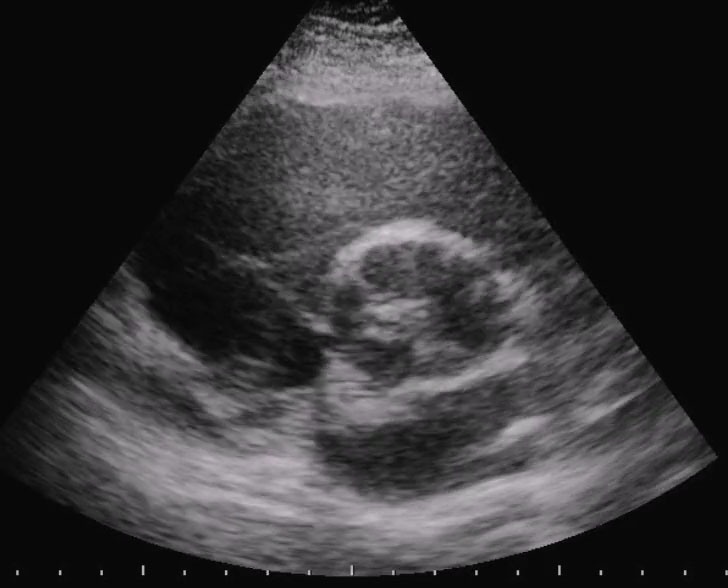

Titolo:

Insufficienza aortica in aorta bicuspide

Autore:

Chiara Bencini